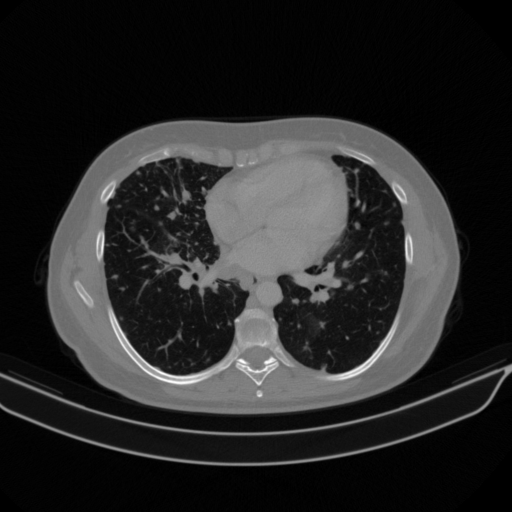

Targeted Slice 70 - Lung Window Analysis (Generated vs Real Venous)

0.728

Lung SSIM

109.0

Lung RMSE

48.5

Lung MAE

Average Lung Window Metrics Across All Slices (133 slices) - Generated vs Real Venous

0.727

Lung SSIM (Avg)

108.6

Lung RMSE (Avg)

46.1

Lung MAE (Avg)

Original NATIVE CT scan (input)

No window - Raw intensity values

Lung window (WL -600, WW 1500 β†’ Low βˆ’1350, High +150)